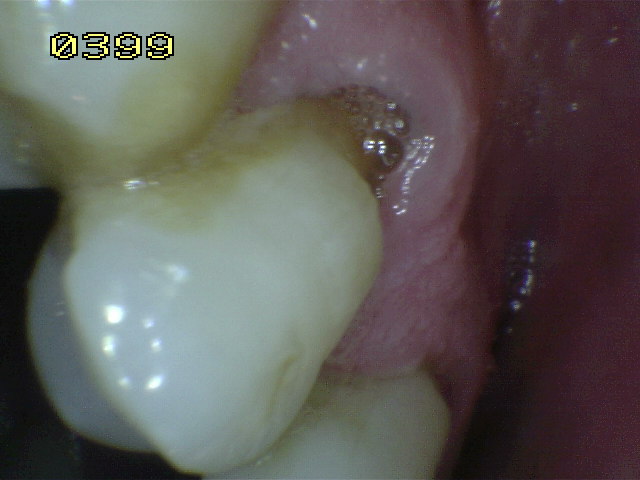

Código E:

Si la

superficie de la raíz

no puede ser visualizada

directamente como resultado

de la falta de la recesión

gingival,

entonces es

excluida. Ver imagen

inferior izquierda. Superficies

cubiertas completamente por

cálculos deben ser

removidos antes de

determinar el estado de

la superficie.